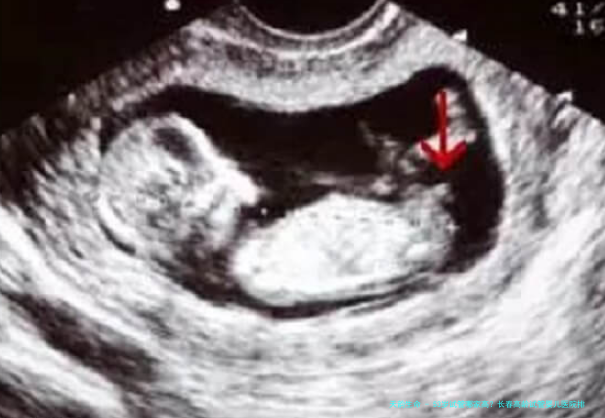

53岁的女性进行试管婴儿,面临着卵巢功效下降、卵子质量减少、子宫内膜容受性变化等多重挑战。选择医院时,不能单看整体,更要查考其针对高龄患者的个性化方案制定本事、胚胎培育技术(如是否展开三代试管PGT)、以及应对并发症的丰富经验。一个的生殖医学中心,应当具备强大的多学科协作能力,能够为高龄女性提供从怀孕前调护到孕期安胎的全面性支持。